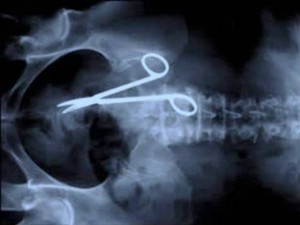

Xtreme X-rays: How Did That Get In There?! Andrew | February 10, 2014 | Did You Know?, Humor | No Comments [tps_title]Surgery Gone Wrong[/tps_title] How long can you survive with a pair of surgical scissors wedged in your abdomen? Apparently 18 months! At least that’s how long this poor Australian lasted before finally feeling the pain. Previous 1 2 3 4 5 6 7 8 9 10 11Next Related Posts The Podcast Revolution- 5 Main Benefits of Podcasting No Comments | Jun 12, 2017 How to be a Whizz at Science No Comments | Dec 8, 2019 The Writing Is On The Wall: Bathroom Graffiti Artists No Comments | Jan 14, 2014 How Much Filling Do I Need for a Bean Bag? No Comments | Nov 26, 2019 Add a Comment Cancel replyYou must be logged in to post a comment.